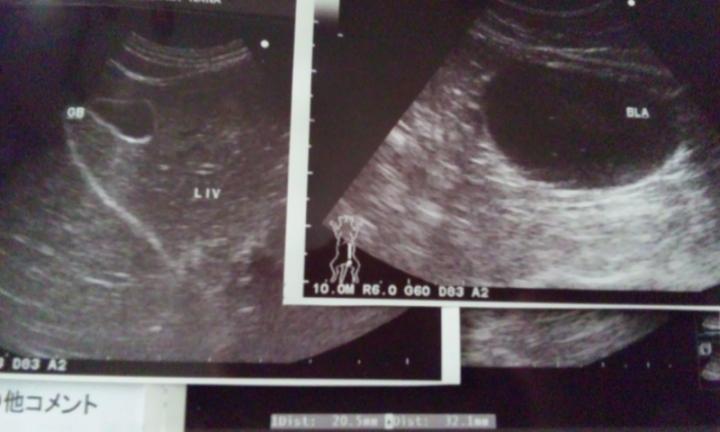

↑エコーの写真

これがナナのおなかの中かぁー。。上の光ってる線のとこは脂肪です;

実は膀胱に何かが写っていたんですが、後日検尿していただいたところ問題なしとのことでした。

ナナの内臓は正常、FeLV・FIVともに陰性